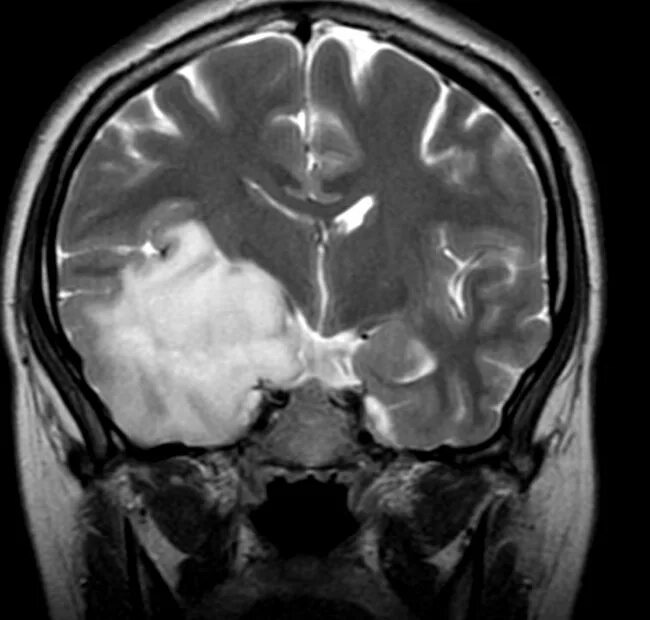

Бластома мозга